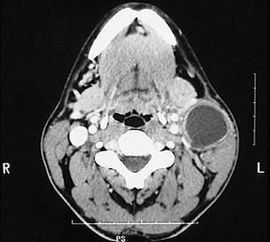

先天性第一鰓裂囊腫廈瘺管臨床少見(jiàn),易誤診、誤治。影像學(xué)檢查是術(shù)前確診的重要依據(jù);充分的術(shù)前準(zhǔn)備和合理的手術(shù)方案是該病治愈的關(guān)鍵,完整切除囊腫度瘺管是避免復(fù)發(fā)的重要措施。